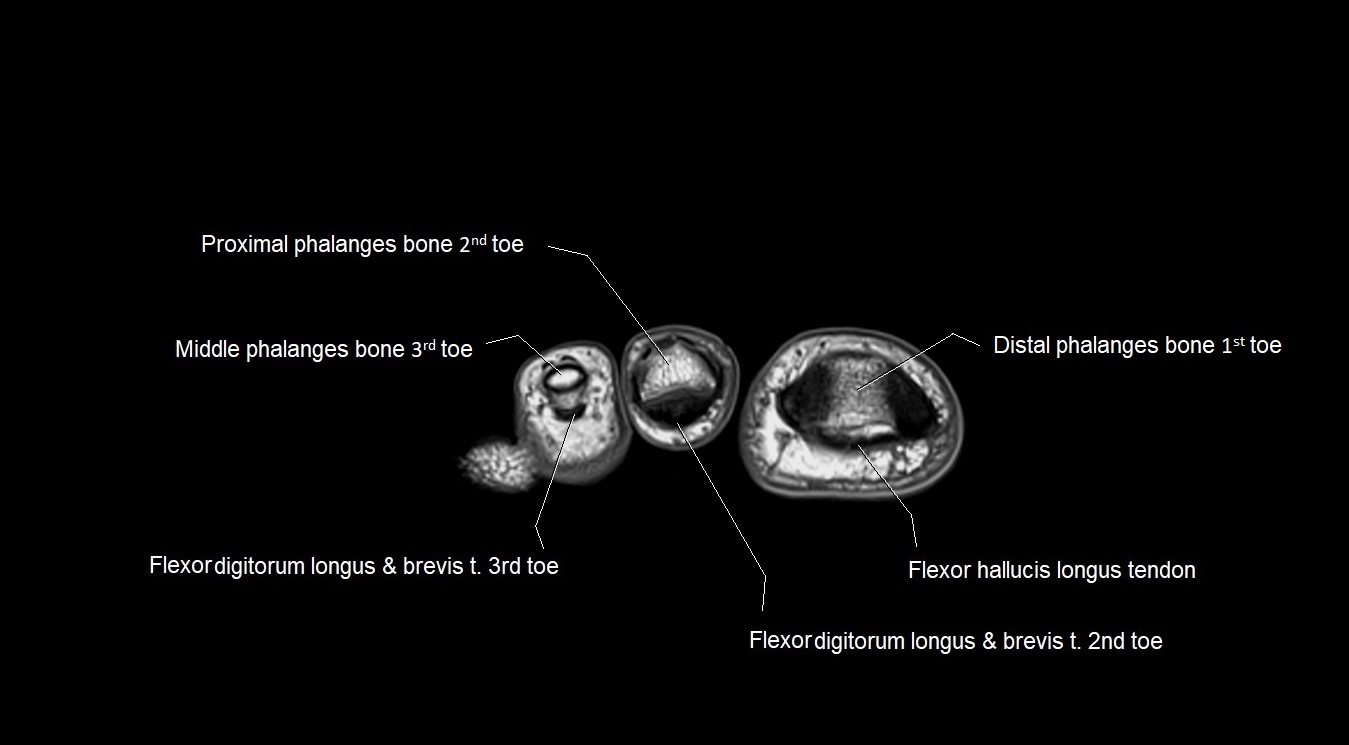

MRI image